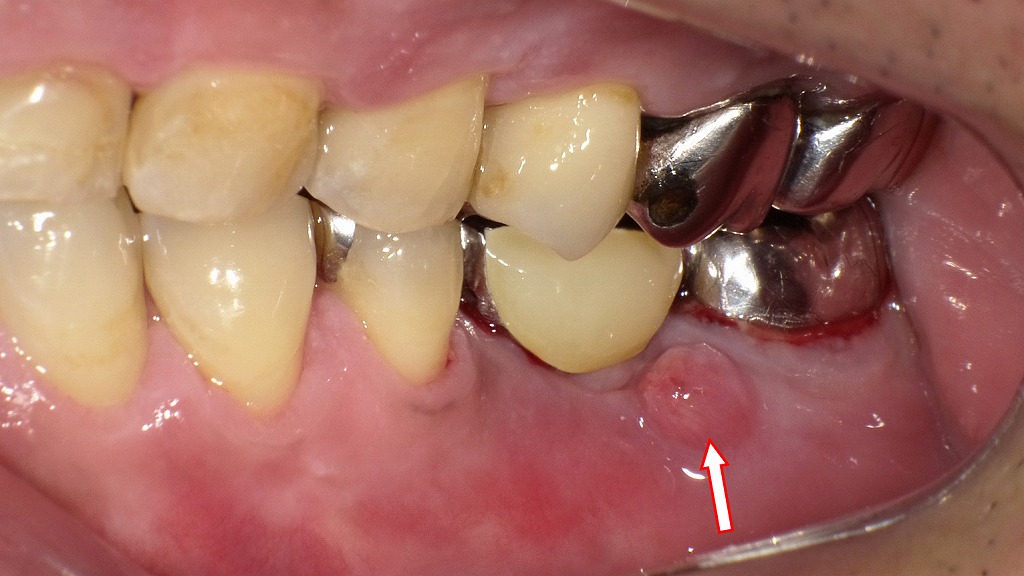

この画像は、左下臼歯部(特に左下7番周囲)の口腔内を示しています。以下に詳細を解説します。

左下7番(下顎第二大臼歯)の根尖(歯の根の先)に関連する炎症性変化が見られ、**歯肉にフィステル(瘻孔)**が形成されています。矢印の先に見える小さな赤い隆起がそれです。

■ フィステル(瘻孔)の形成

- 歯の根の先に感染が起こり、膿が歯肉を通って排出されるために**通路(瘻孔)**ができています。

- この状態は、根尖性歯周炎や根管内感染に起因することが多いです。

- 矢印部には膿の排出口が確認でき、周囲粘膜に軽度の発赤と腫脹が見られます。

■ 原因歯:左下7番

- 金属冠が装着されており、根管治療済みの可能性が高いですが、内部感染が再発していると考えられます。

- 根尖部に慢性的な感染巣(根尖病変)が存在し、排膿によってフィステルが形成された状態。

💨 臨床的懸念点

- 膿が排出されている間は一時的に痛みが軽減することがありますが、根本的な感染は残存しています。

- 感染源からの膿やガスが**口臭(膿臭)**の原因となることが多いです。

- 放置すると骨吸収が進行し、根尖病変の拡大や隣在歯への波及のリスクがあります。

🩺 治療のポイント

- 原因歯の根管再治療(再根管治療)

→ 感染源の除去が最も重要です。 - 必要に応じて外科的歯根端切除術を検討。

- 感染が強い場合は抗菌療法の併用。

- 治癒後にフィステルは自然閉鎖しますが、再発防止のための定期管理が必須です。